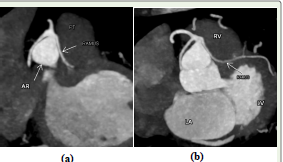

Figure 2: (a) and (b) show oblique reformatted CT angiographic image

showing the single coronary artery (SCA) arising from the right coronary

sinus. The vessel divides into the right coronary artery (RCA), left anterior

descending artery (LAD), left circumflex artery (LCx), and a prominent ramus

intermedius (RI). No ostia are seen in the left coronary sinus.

Abbreviations: SCA – single coronary artery; RCA – right coronary artery;

LAD – left anterior descending artery; LCx – left circumflex artery; AR- Aortic

Root; LA- left atrium; PT - pulmonary trunk